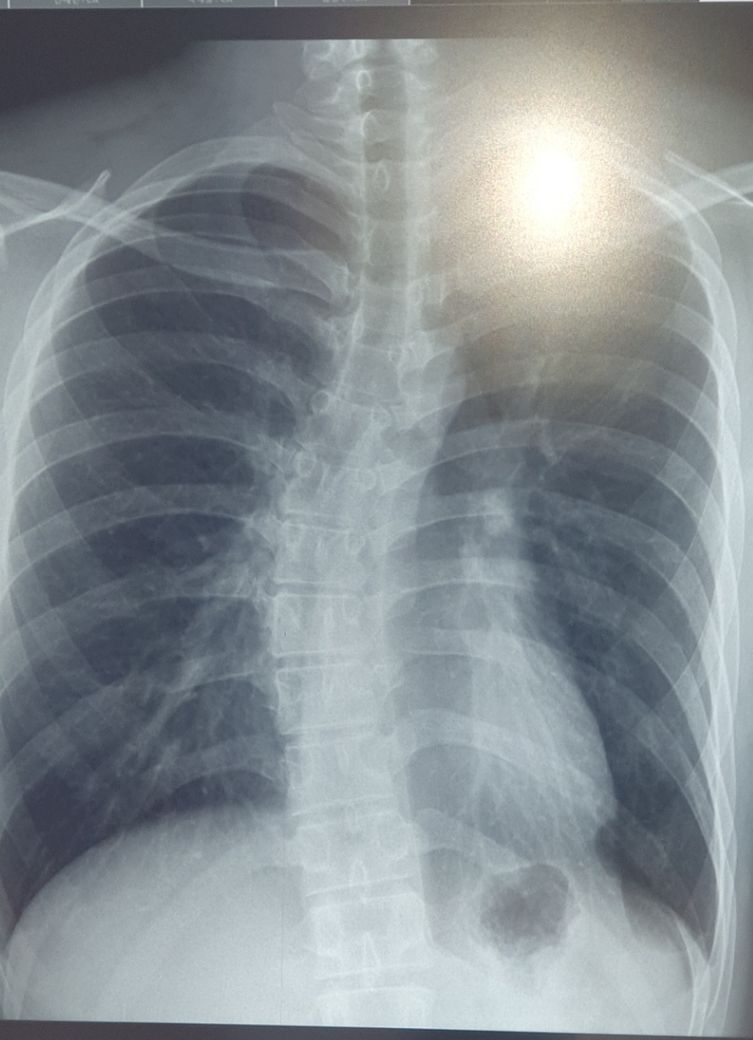

측만증이 있습니다. 운동을 해도 괜찮은 상태인가요?

푸쉬업이나 턱걸이를 해도 괜찮은 상태인지 궁금합니다

괜히 상태가 더 안좋아지거나 근육이나 뼈에 무리가 가지는 않을까 걱정이 되는데요,

또 운동으로 근육이 강화되면 측만증에 도움이 되는지도 알고 싶습니다

측만증이 있으시다 하더라도 현재 디스크 등의 병변이 없고 통증이 심하시지 않으시다면 규칙적인 운동을 통해 등, 허리 근육 강화를 시행하여 주시는 것이 추후 관리에 도움이 되실 것 같습니다.